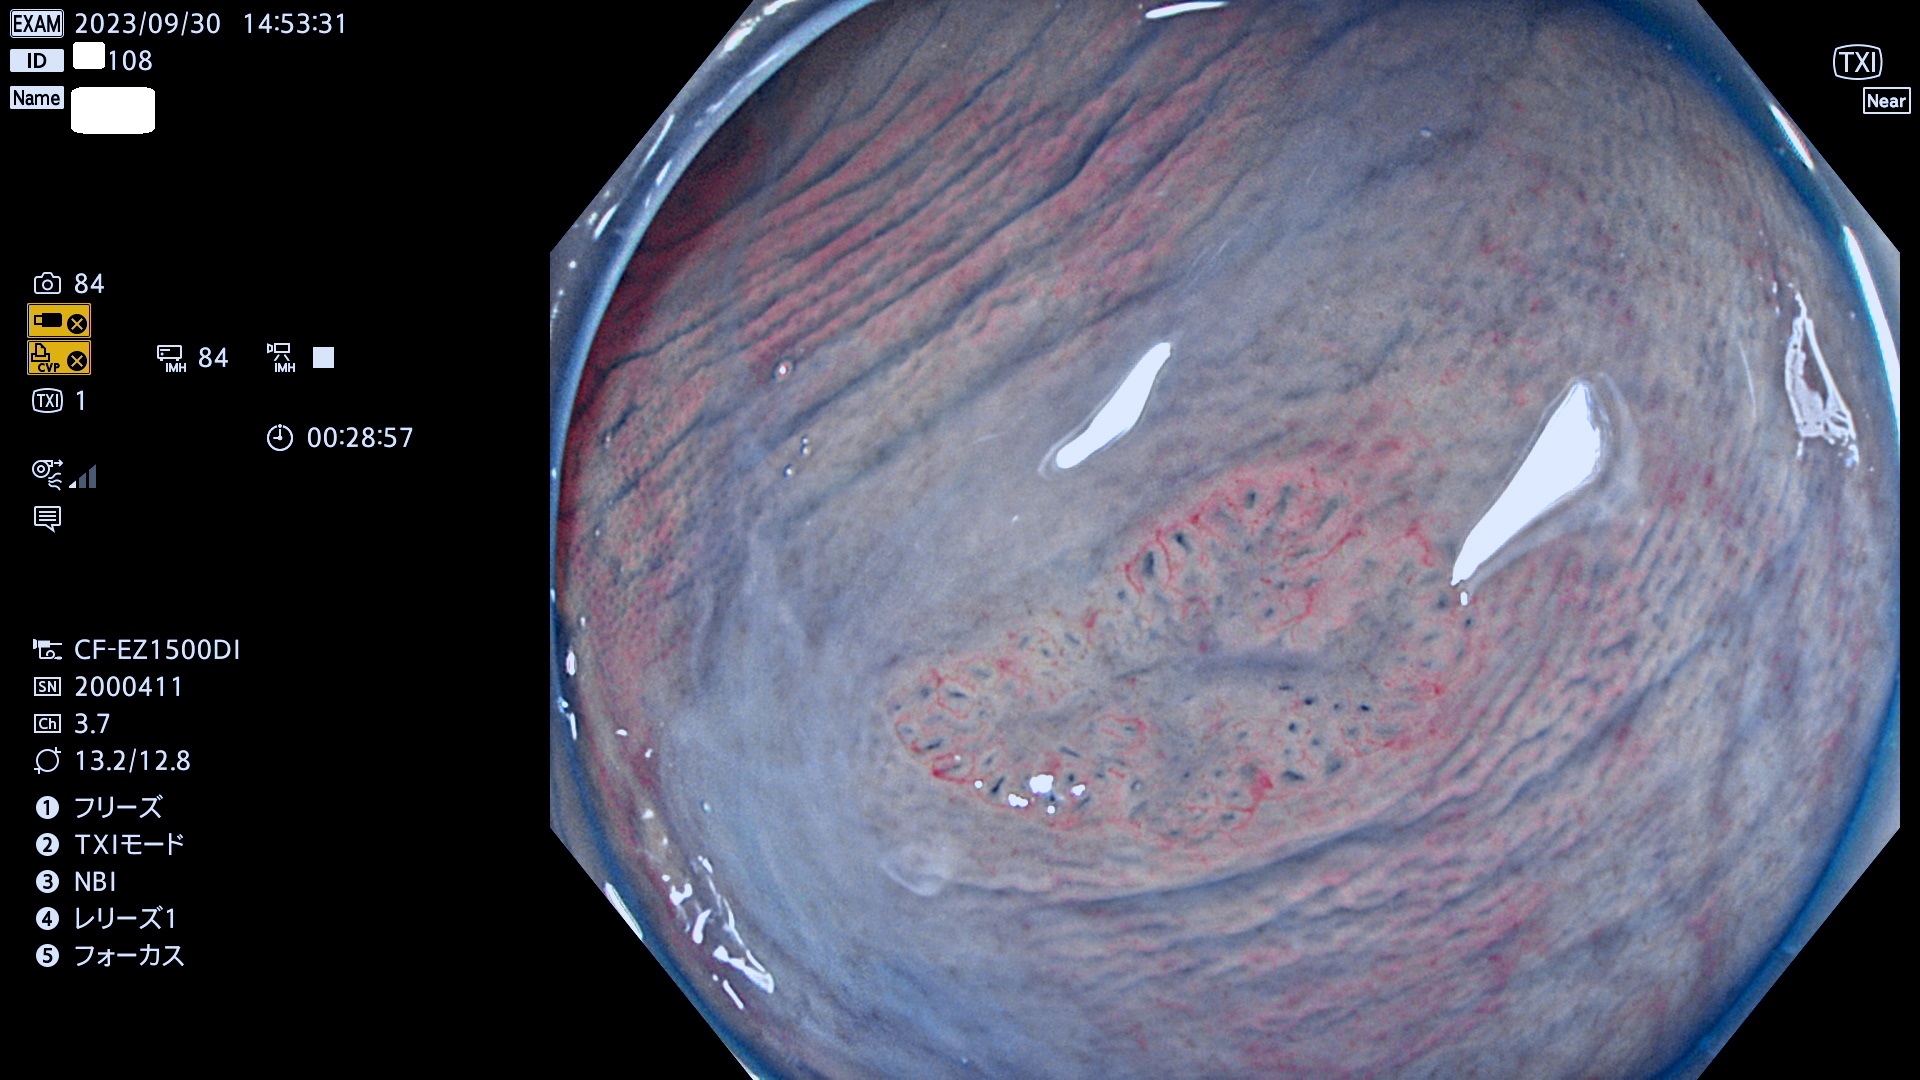

表面型腺腫(Flat Adenoma)の中で、完全に平坦な物をUb、陥凹している物をUcと呼びます。平坦隆起型(Ua)よりも、発見が難しく危険な病変です。このタイプは「内視鏡後・大腸癌の重要犯人」であり、この発見率は「腺腫発見率」よりも、重要な意味があります。

毎週の検査(木・金・土・日)に発見されたUb、Uc型・腺腫を、その週の日曜の夜にUPし1週間、提示します。

抽出の対象期間 2023年9月28日(木)〜10月1(日)の4日間(48件の検査)8件